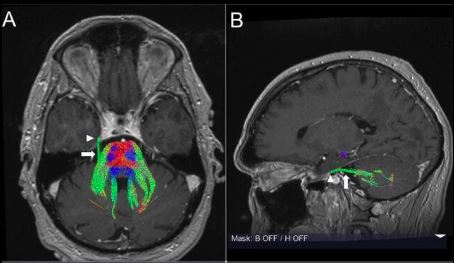

Trattografia del nervo trigemino alla root entry zone (REZ) con ricostruzione DTI su risonanza magnetica, visualizzazione delle fibre nel punto di ingresso nel tronco encefalico

Ricostruzione trattografica (DTI) del nervo trigemino alla root entry zone (REZ): le fibre nervose sono visualizzate nel punto di ingresso nel tronco encefalico, sede critica per l’insorgenza della nevralgia del trigemino e per il conflitto neurovascolare.